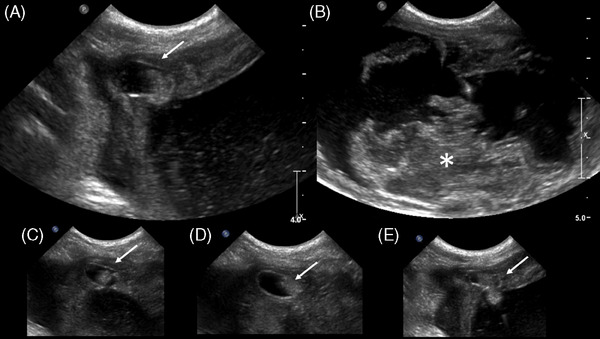

A young, intact, female, American Bulldog was presented for hemorrhagic vaginal discharge. Anemia, thrombocytopenia, leukocytosis with neutrophilia, azotemia, and electrolyte disturbances were detected in the bloodwork. A urachal diverticulum with concurrent uterine distention was identified by ultrasonography and CT. The diverticulum was excised in surgery, and an ovariohysterectomy was performed. Histopathological examination confirmed an abscessed bladder wall with concurrent pyometra.

Abstract Image